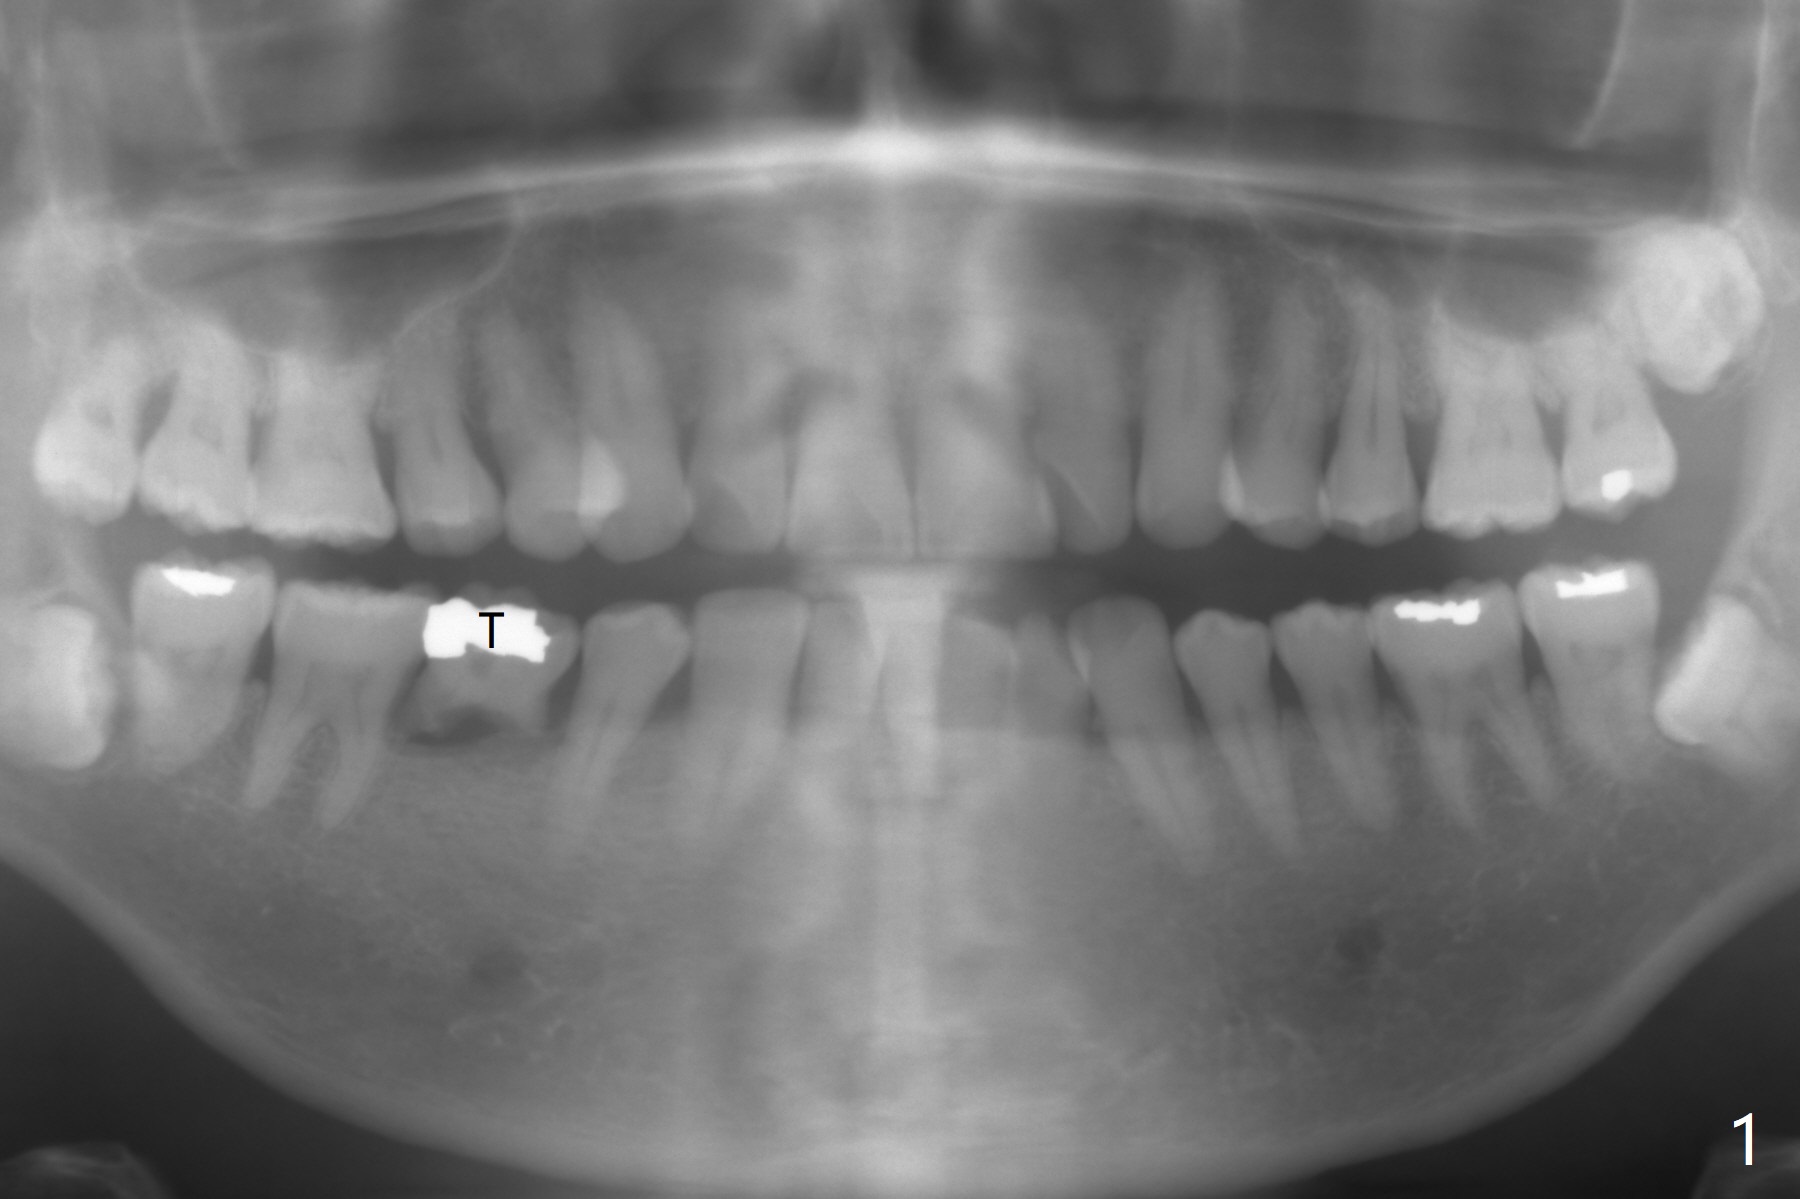

A 51-year-old man has a mobile 2nd primary molar (Fig.1 T). The latter is much wider than the 2nd premolar. Since there is crowding in the lower anterior region, it is the best to have limited orthodontic treatment to use the extra space at T to alleviate crowding anteriorly after implant osteointegration. Although the patient has no intention for orthodontics, an implant will be placed distal (Fig.2 green). To prevent periimplantitis, make sure that the implant is placed below bone. Encourage the patient to brush normally over the provisional once there is no pain. Use Rongeur to remove the septal bone before osteotomy. Try IS implants if they arrive.